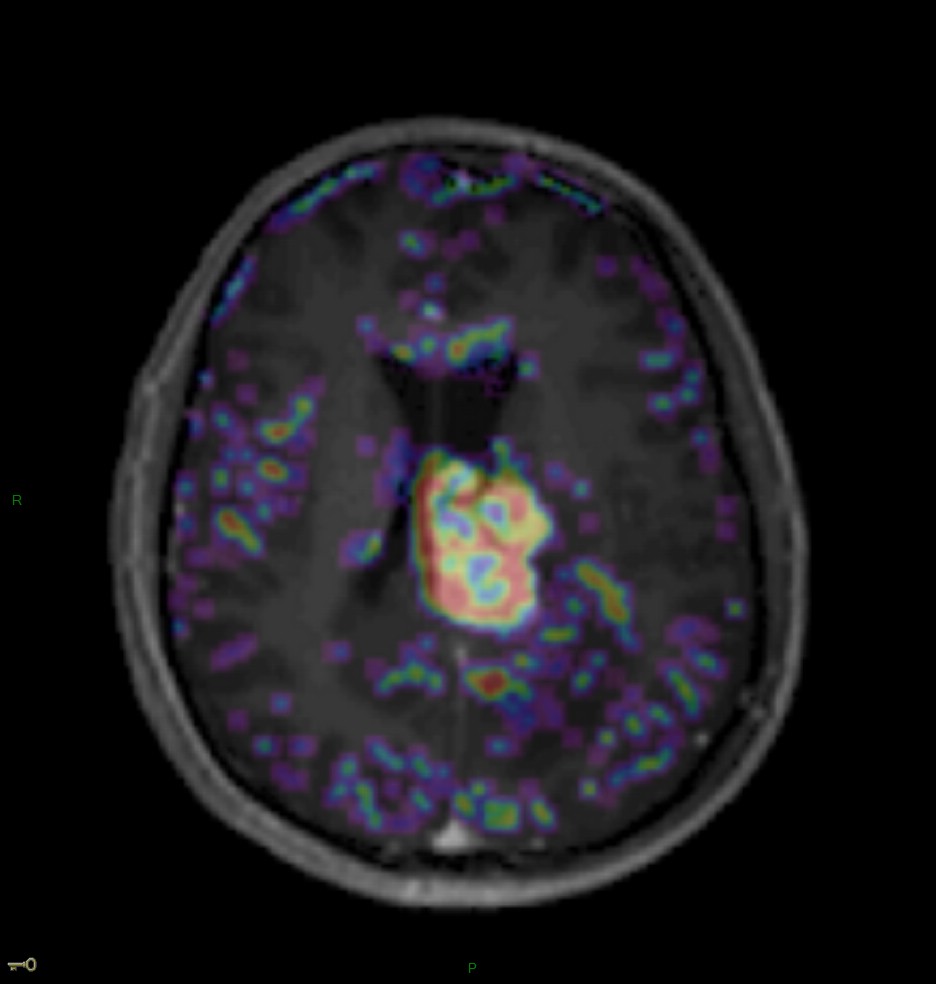

fBV – Localisation cérébrale d’un lymphome B à grandes cellules diffus, EBV négatif